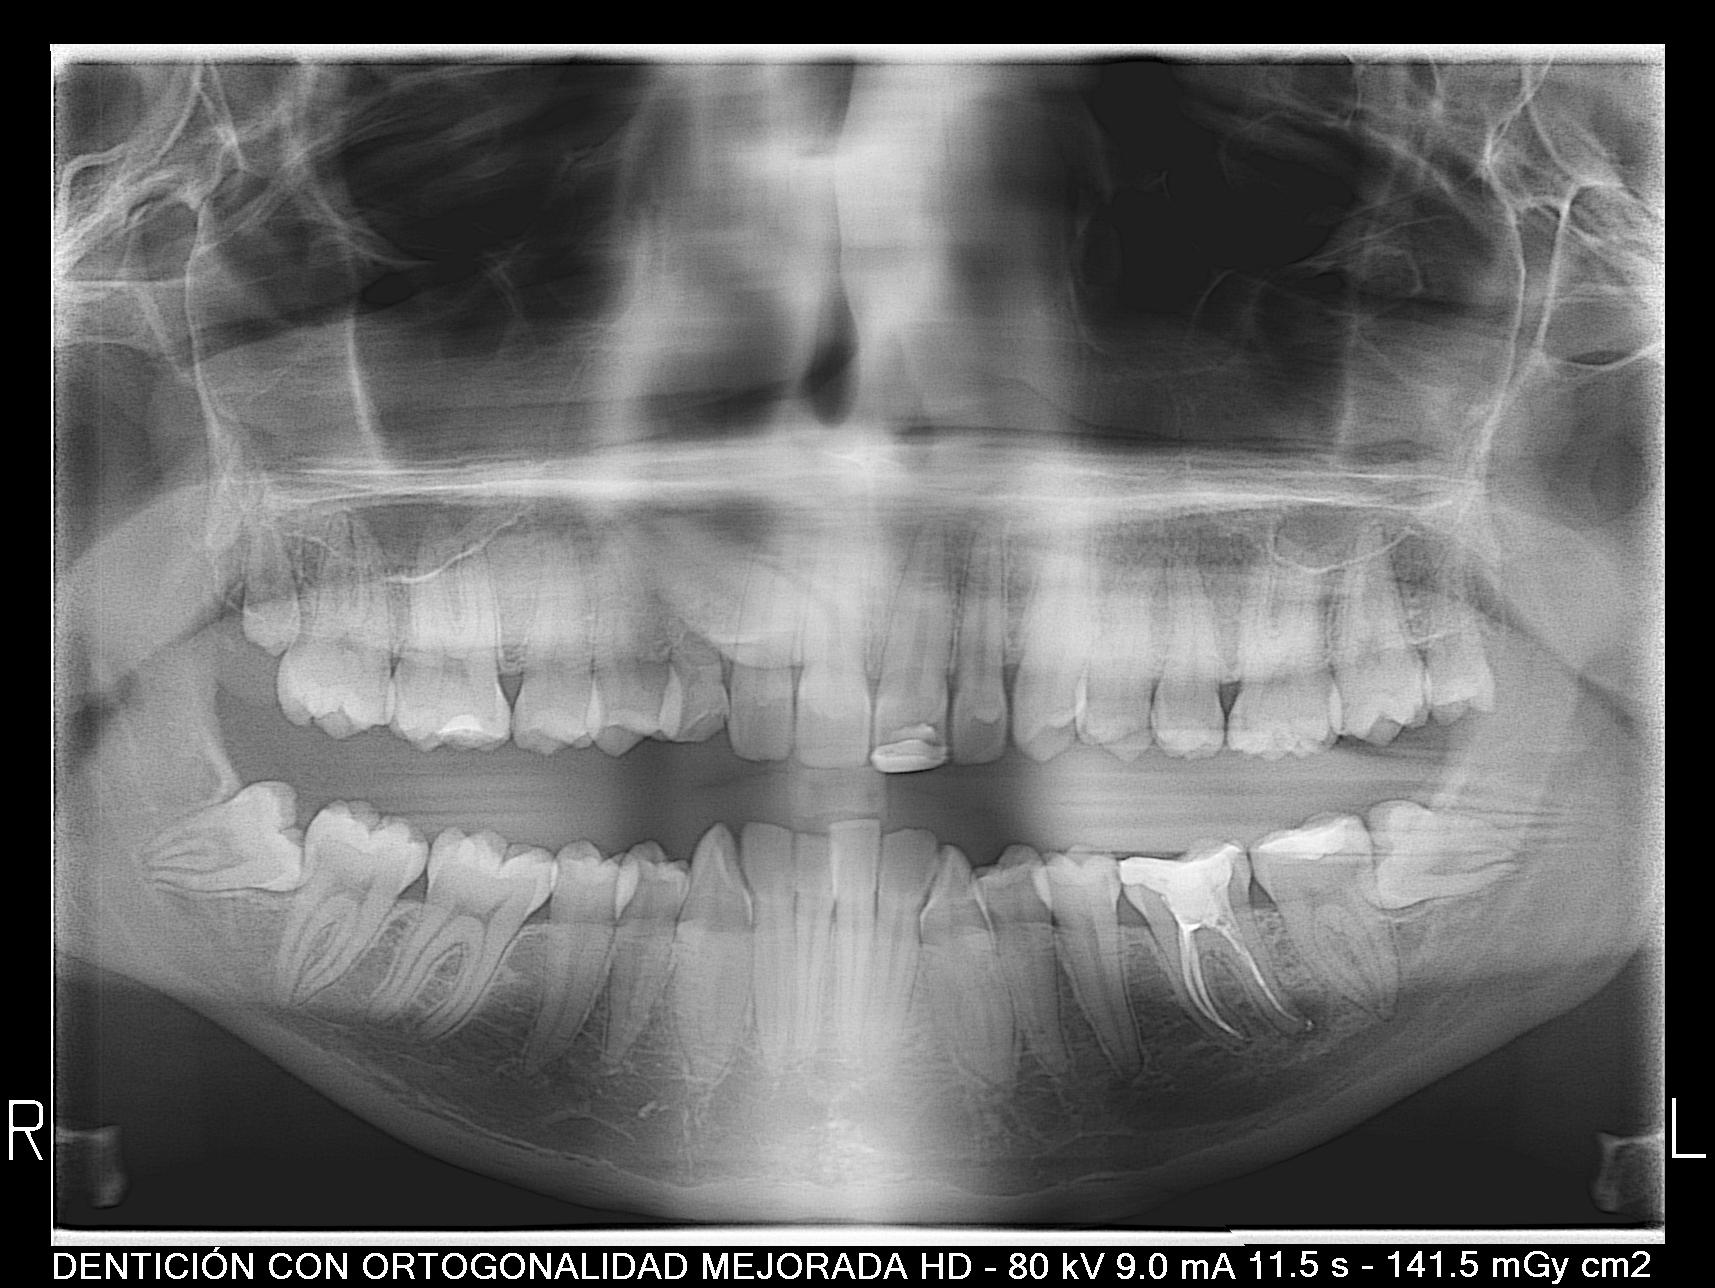

Se muestra el caso de una paciente con un canino incluido en el paladar (pieza 13).

Como principal escollo, nos encontramos con una activa enfermedad periodontal y una deficiente higiene oral. También hay otros problemas secundarios que no hay que desdeñar: apiñamiento inferior con Bolton; leve apiñamiento anterosuperior; malposición de los cordales 48 y 38; rotación del 23; ligera clase II en el lado derecho entre otros. De primera hora se le comunicó a la paciente que antes de empezar el tratamiento de ortodoncia era necesario realizarse de periodoncia, y que después el/la profesional de esta disciplina, nos confirmara que podíamos empezar nuestro trabajo. También, avisamos de la importancia, de que durante el tratamiento, era necesario acudir al periodoncista cada 2 meses y mejorar la higiene oral.

B) ¿Cómo se diagnóstica? Palpación a los 9-10 años; ortopantomografía; CBCT.

-Particularmente, cuando reconozco mediante la palpación o la ortopantomografía que hay una canino incluido por palatino, por protocolo, como en este caso, hago un CBCT. El motivo es porque esta prueba diagnóstico nos permite reconocer de una manera tridimensional el lugar del canino en la boca.

C) ¿Está el canino incluido por palatino asociado a otros posibles hallazgos clínicos? Si. ¿Cuáles?  Disto angulación de los segundos premolares; infra oclusión de dientes temporales; microdoncia de incisivos laterales superiores; agenesia de un incisivo lateral superior o de terceros molares.

-En este caso no se encontraron ninguno de eso hallazgos clínicos frecuentes.

Atendiendo a estos criterios, en nuestro caso, el pronóstico es bueno. Ya que tres de los cuatro criterios son favorables: el ápice se encuentra en una posición ideal, la distancia al plano oclusal no es mayúscula y la inclinación es mayor a 31 grados. Solo la posición de la corona cerca de la línea media aumentaría la dificultad.